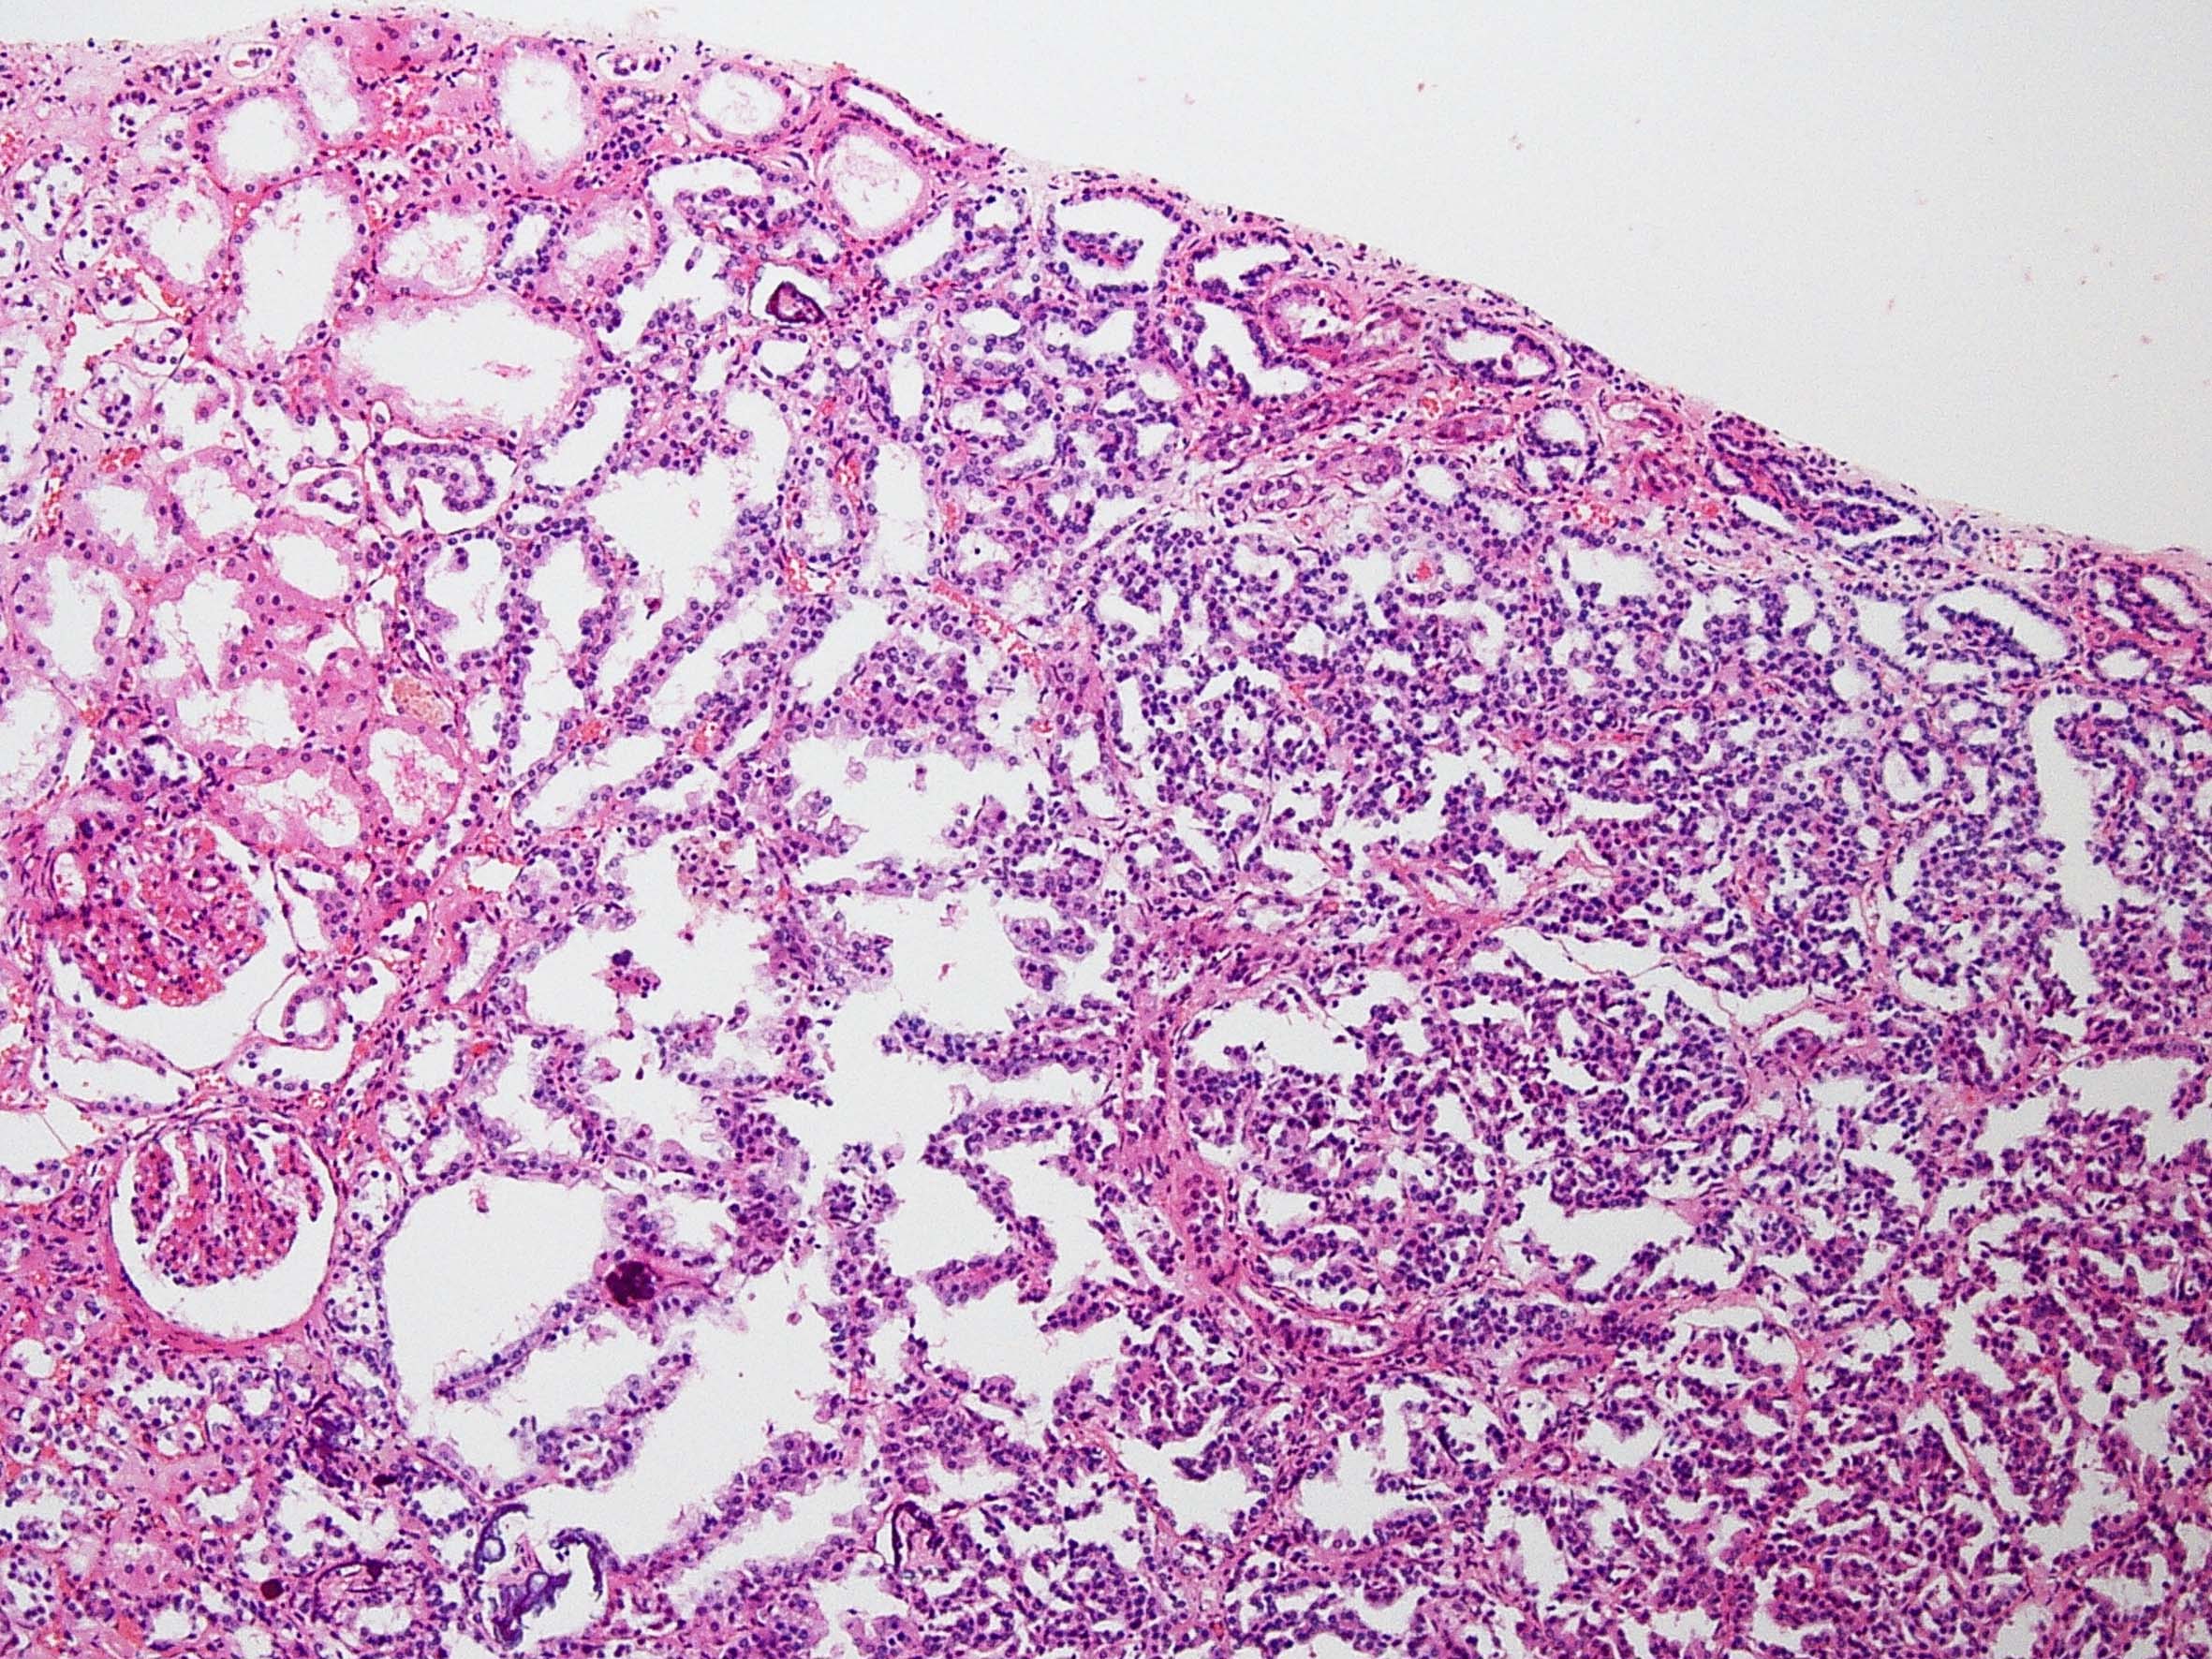

Classification of renal tumors

Case ID: 228